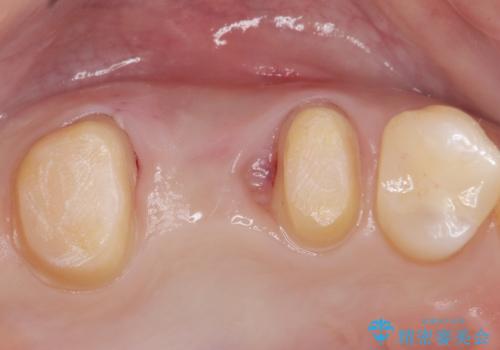

- 銀の詰め物、被せ物を白くしたいとのことで来院。

銀のところはインレーブリッジになっており、外してブリッジを入れたいが奥の歯が前に倒れ込んでおり、

ダミーの歯の部分(ポンティック)のスペースが狭いため無理やり作るとインレーブリッジと同じように小さい歯が出来てきます。